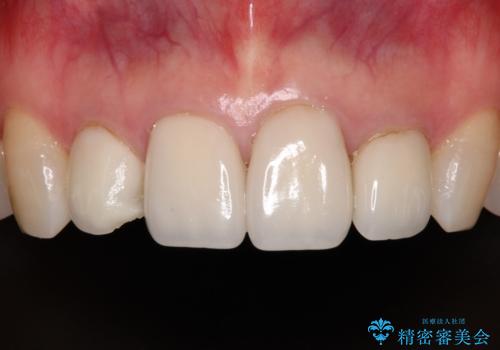

欠けてしまったセラミッククラウン 周囲のクラウンと同様の色彩で再製作

- 上顎4前歯に装着されているセラミッククラウンのうち、ひとつが欠けてしまったとのことで来院された患者様です。

土台となっている歯には問題がないため、周囲のセラミッククラウンと色調が合うように、オーダーメイドタイプのセラミッククラウンにて補綴治療を行うこととしました.

欠けてしまったセラミッククラウンはガラス系セラミッククラウンであったため、今回製作する歯は、強度の強いジルコニアセラミッククラウンとしました。

クラウンの種類は異なりますが、色調の適合したクラウンを装着することができました。